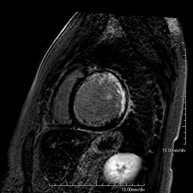

És una prova diagnòstica no invasiva que obté informació morfològica i funcional del cor i les estructures adjacents. D'aquesta manera es poden diagnosticar diferents patologies congènites i adquirides, o bé realitzar controls en pacients amb patologia prèvia ja coneguda. En la gran majoria de casos és necessari l'ús de contrast intravenós (Gadolini) per completar l'estudi, un tipus de contrast que rarament produeix reaccions adverses. Durant la prova el tècnic li demanarà diverses vegades que aguanti la respiració durant 10-15 segons per obtenir les imatges tant clares sigui possible. No es necessita preparació prèvia per part del pacient. La durada de la prova és de 45 – 60 aproximadament. Està contraindicada en pacients amb marcapassos. El pacient haurà d'avisar en cas que porti implants metàl·lics i/o clips quirúrgics. - RM cardíaca amb estrès miocardi

- RM Cardíaca

És una prova diagnòstica no invasiva que obté informació morfològica i funcional del cor i les estructures adjacents. D'aquesta manera es poden diagnosticar diferents patologies congènites i adquirides i realitzar controls en pacients amb patologia prèvia ja coneguda. En la majoria de casos és necessari l'ús de contrast intravenós (Gadolini) per completar l'estudi, un tipus de contrast que estranyament produeix reaccions adverses. Durant la prova el tècnic li demanarà diverses vegades que aguanti la respiració durant 10-15 segons per obtenir les imatges el més clares possible. No requereix preparació prèvia per part del pacient. La durada de la prova és d'aproximadament 45-60 minuts. Està contraindicada en pacients amb marcapassos i el pacient ha d'indicar si és portador d'implants metàl·lics i/o clips quirúrgics. - RM Cardíaca amb estrès miocàrdic